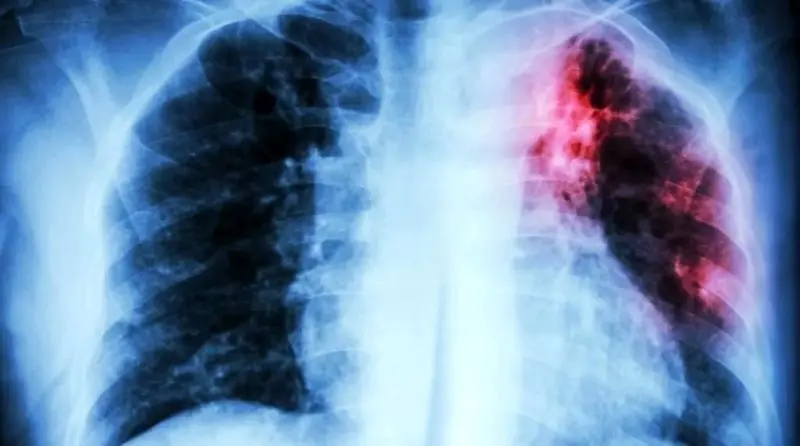

سازمان بهداشت جهانی (WHO) اعلام کرد که سل همچنان به عنوان کشنده ترین بیماری عفونی در جهان جایگاه مرگبار خود را حفظ کرده و در سال 2024 1.23 میلیون نفر را به کام مرگ کشانده است.

بر اساس گزارش جهانی سل در سال 2025، این بیماری عفونی کشنده ترین بیماری عفونی سال گذشته بود. البته برای اولین بار از زمان همه گیری کووید-19، جهان شاهد کاهش همزمان موارد سل (نزدیک به 2 درصد) و مرگ و میر ناشی از آن (3 درصد) بوده است. اما WHO هشدار می دهد که این دستاوردها شکننده هستند.

مدیرکل سازمان جهانی بهداشت گفت: کاهش موارد جهانی سل و پیشرفت در آزمایش و درمان همه خبرهای خوشایند است، اما چنین پیشرفت هایی به معنای پیروزی نیست. او می گوید که سل، اگرچه قابل پیشگیری و درمان است، اما همچنان سالانه جان بیش از یک میلیون نفر را می گیرد و آن را به یک مشکل جدی تبدیل می کند.